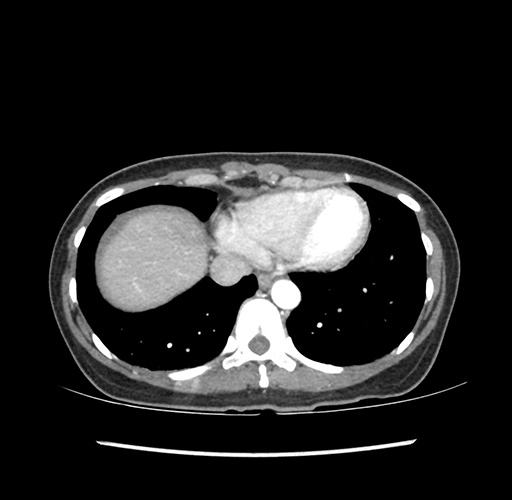

Imaging Analysis

Look through the patient's CT scan to identify any areas of concern for the necessary procedure.

Based on your CT findings, which issue(s) would give reason for "planned slowing down moment(s)" in this case?